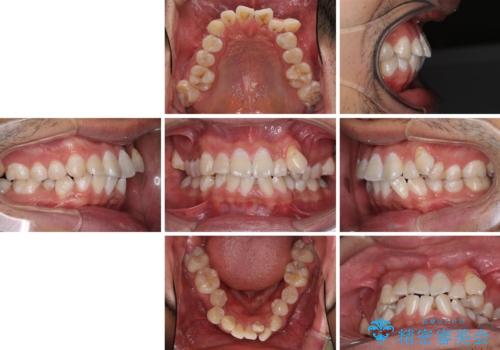

- 前歯の叢生と八重歯を気にして来院された患者様です。

叢生が強く、奥歯の咬合も左右差が大きかったため、上下左右4本を抜歯して、ワイヤー矯正を行うこととしました。